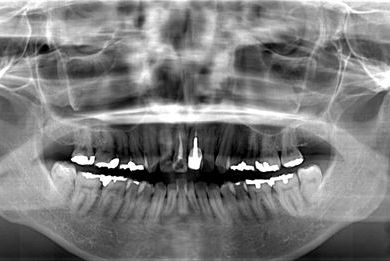

全顎矯正治療+セラミック治療

| 性別/年齢 | 女性 / 35歳 | ||||||||||||||||||||||||||||||||

| 主訴 | 出っ歯 上顎前歯の並び | ||||||||||||||||||||||||||||||||

| 治療方針 | 上下歯牙がだいぶ前にでていて口が閉じづらい状態でした。なるべく金属が入っている歯を抜歯したいので、上下左右第二小臼歯を抜歯して、その隙間を利用して、口元をさげていきました。また、口元を最善の状態にうるために、抜歯スペースを使用したあと、上下左右のインプラントアンカー(釘)でより一層口元を後ろにさげていきました。ただの抜歯ケースよりだいぶ口元が下がっているのが分かります。抜歯したスペースががたつき(叢生量)で使用してしまう場合には、このような方法でより口元をさげることができます。お顔立ちがとてもよくなりました。とても協力していただけたので、しっかりと良くなることができました。 | ||||||||||||||||||||||||||||||||

| 治療内容 | 唇側矯正(ホワイト・上下左右第二小臼歯抜歯・上下インプラントアンカー)、オールセラミッククラウン1本(オールセラミック用土台1本)、ジルコニアフレームオールセラミッククラウン1本 | ||||||||||||||||||||||||||||||||